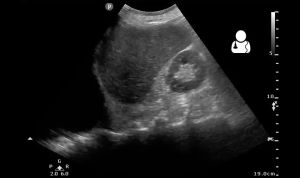

- US